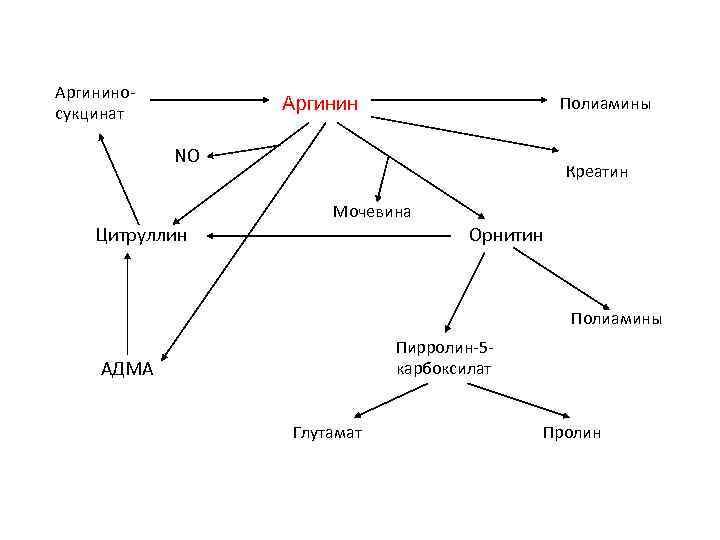

Аргининосукцинат Аргинин Полиамины NO Креатин Мочевина Цитруллин Орнитин Полиамины Пирролин-5 карбоксилат АДМА Глутамат Пролин

Острые воспалительные процессы сопровождаются увеличением активности аргиназ в тканях. Это приводит к активации синтеза полиаминов (стимуляторы клеточного деления) и пролина (синтез коллагена), что, в свою очередь, играет важную роль в заживлении ран, образовании рубца, развитию хронических воспалительных заболеваний и инфекций.